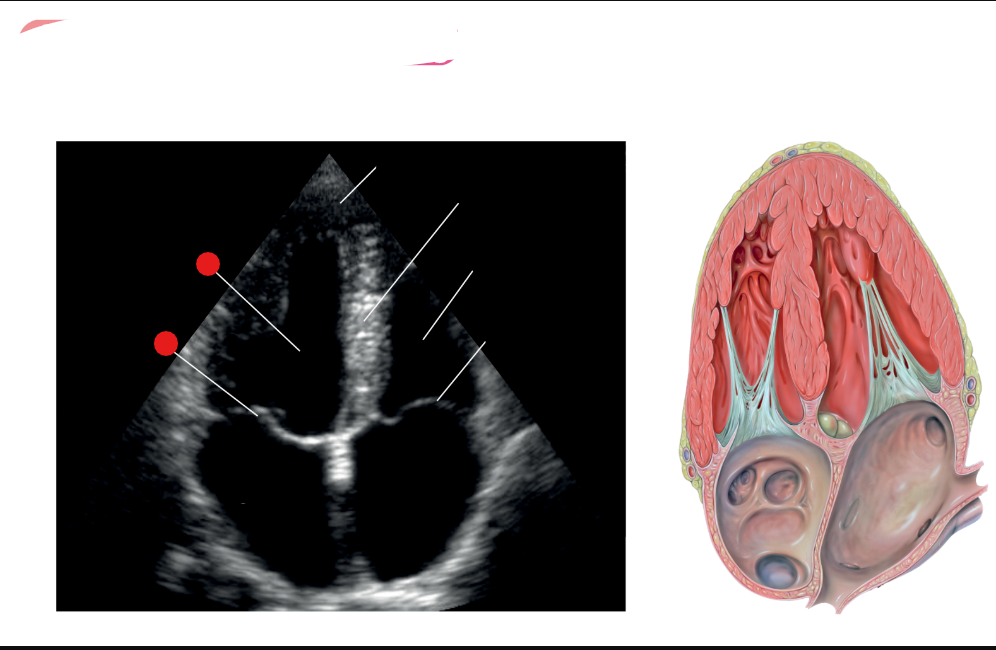

what are the white labels

RV

LA

LV

LVOT

AO

What is this view

parasternal long axis of the heart